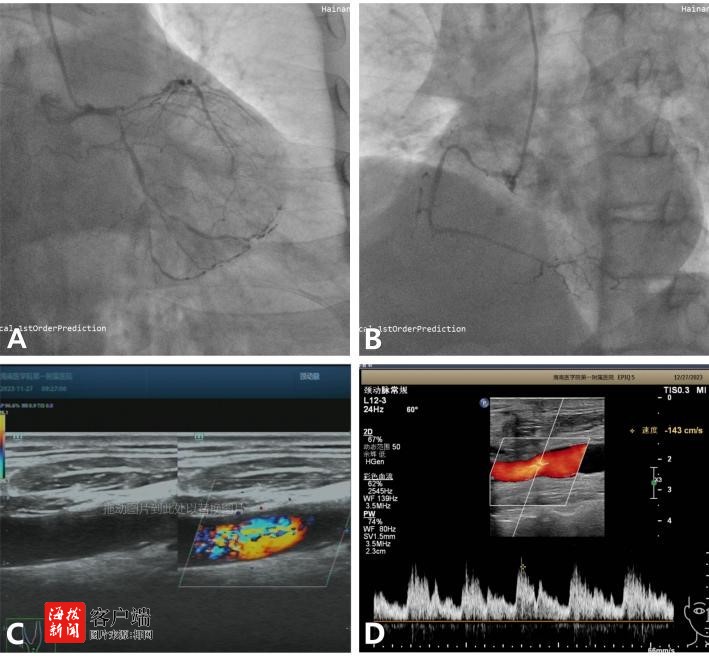

手术过程中,医生们首先通过颈部切口,小心翼翼地剥除了崔老伯颈动脉内的粥样斑块,并用心包片加宽缝合了切开的颈动脉管壁,接着,他们又在心脏跳动的情况下,用左乳内动脉和大隐静脉为崔老伯的心脏搭建了3根新的血管通道,以改善心肌的血液供应。整个手术历时4小时,顺利完成。

术后,崔老伯在心外科监护病房接受了密切的观察和护理。虽然他的肺部功能因多年吸烟和双肺肺大泡而恢复较慢,但在医护人员的精心照料下,他最终成功拔除了气管插管,并逐渐康复。心脏复查结果显示一切正常,颈动脉超声也显示左颈总动脉血流已恢复正常。最终,崔老伯痊愈出院,重新开始了他的生活。